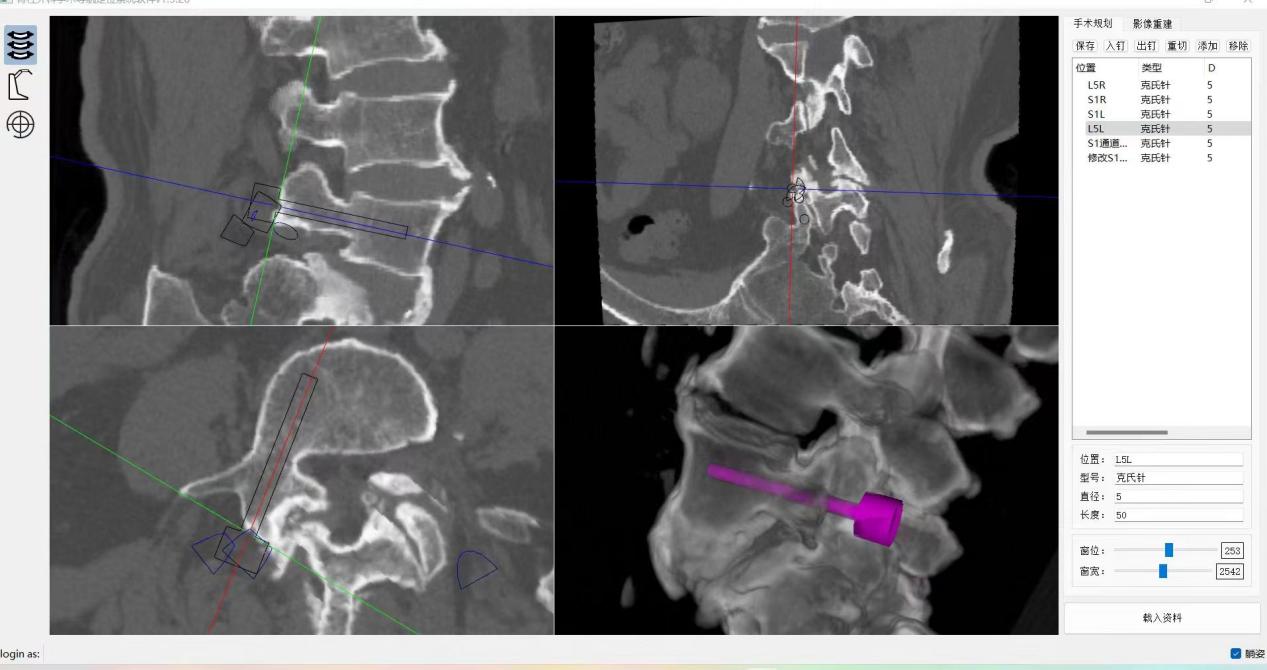

ORTHBOT脊柱机器人术前设计及术中穿刺